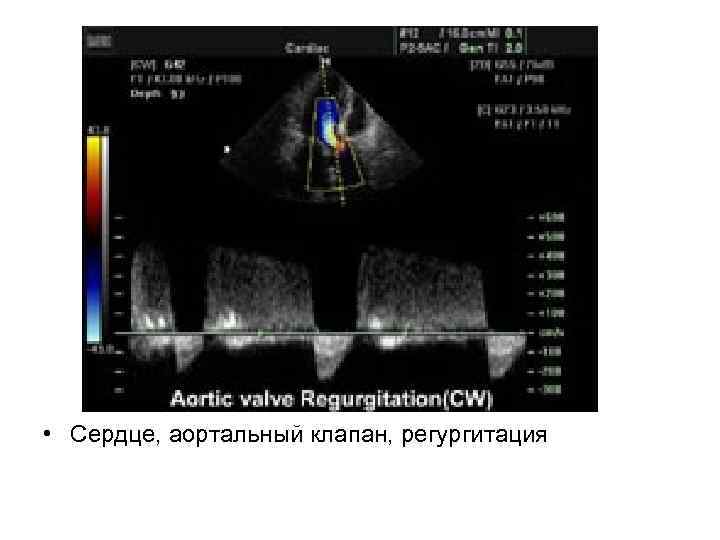

• Сердце, аортальный клапан, регургитация